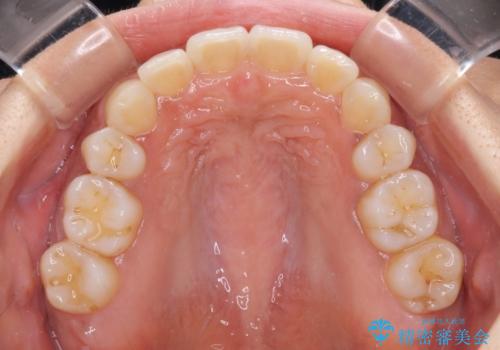

- 以前矯正治療をされていましたが、後戻りが起きたことを気にして来院された患者様です。

全顎的に認められた叢生を改善するため、インビザラインにて治療を行うこととしました。

前歯の叢生の改善を目的として、IPR(歯と歯の間を削る)と歯列全体の後方移動によって歯並びを整えることとしました。

毎日22時間の装着時間を守ってくださいましたが、ハイペースにマウスピースを交換することなく、慎重に治療を進めてくださったので、治療期間はやや長くなりました。

臼歯部も含め、叢生が綺麗に改善され、患者様には大変満足していただきました。